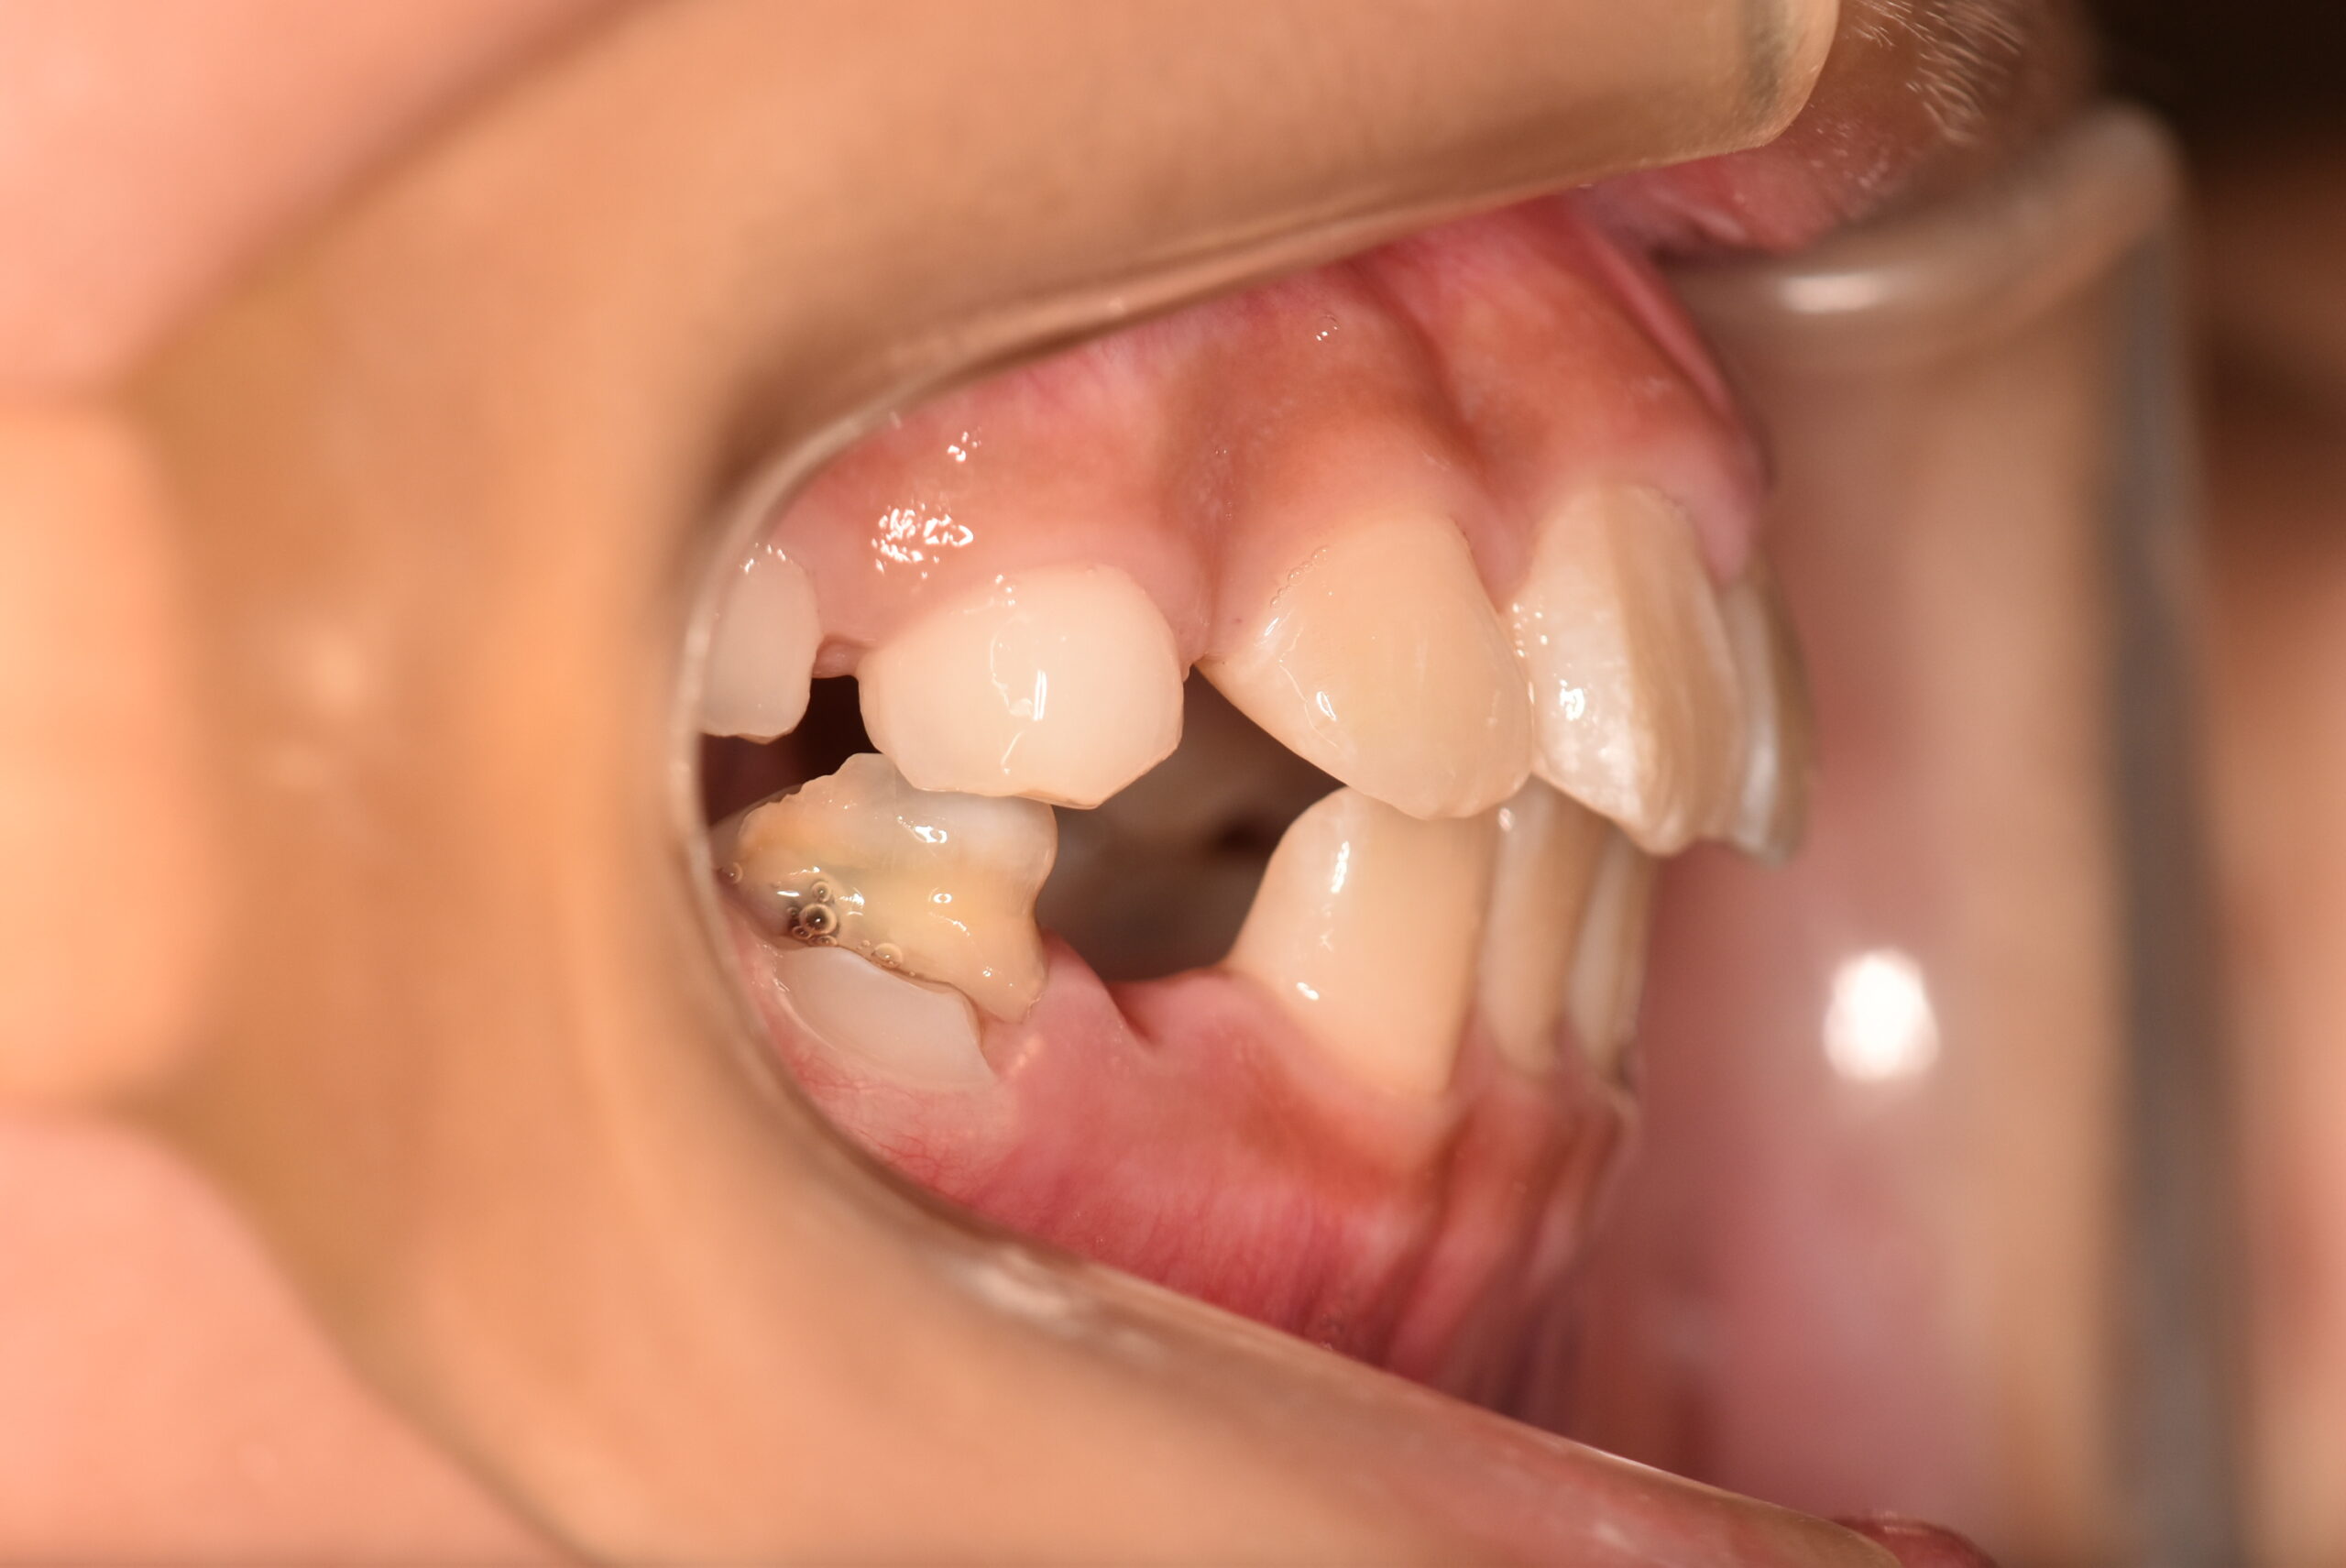

治療内容の詳細 初診時8歳の女児で、正中のズレを気にされ来院されました。

検査の結果、臼歯部交叉咬合を伴うアングルⅠ級不正咬合と診断しました。

治療としてはマウスピース矯正(インビザラインファースト)で配列を行い、上顎の側方拡大と萌出スペースを確保しました。

治療期間は、6ヶ月でした。

今後、側方歯生え変わりまで経過観察を行います。